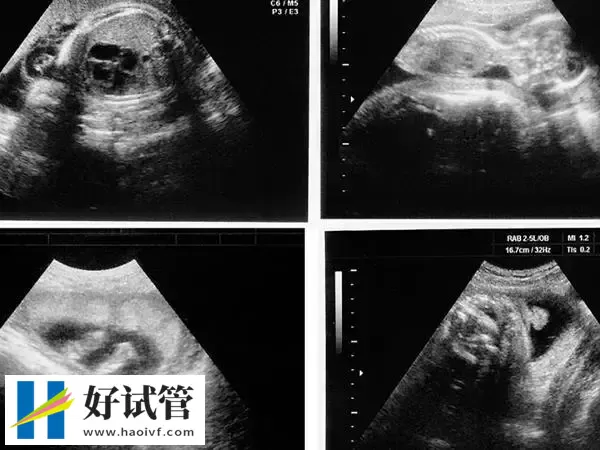

移植第38天孕囊的大小在3cm左右,此时B超下观察胎芽在1.5cm左右,因为移植38天相当于已经正常怀孕8周了,所以这个时期就不能按照孕囊大小计算了,需要按照胎芽或者头臀径计算。孕8周时胎儿长到1.66厘米,胎形已定,可分出胎头、体及四肢,胎头大于躯干。B超可见胎囊约占官腔1/2,胎儿形态及胎动清楚可见,并可看见卵黄囊。